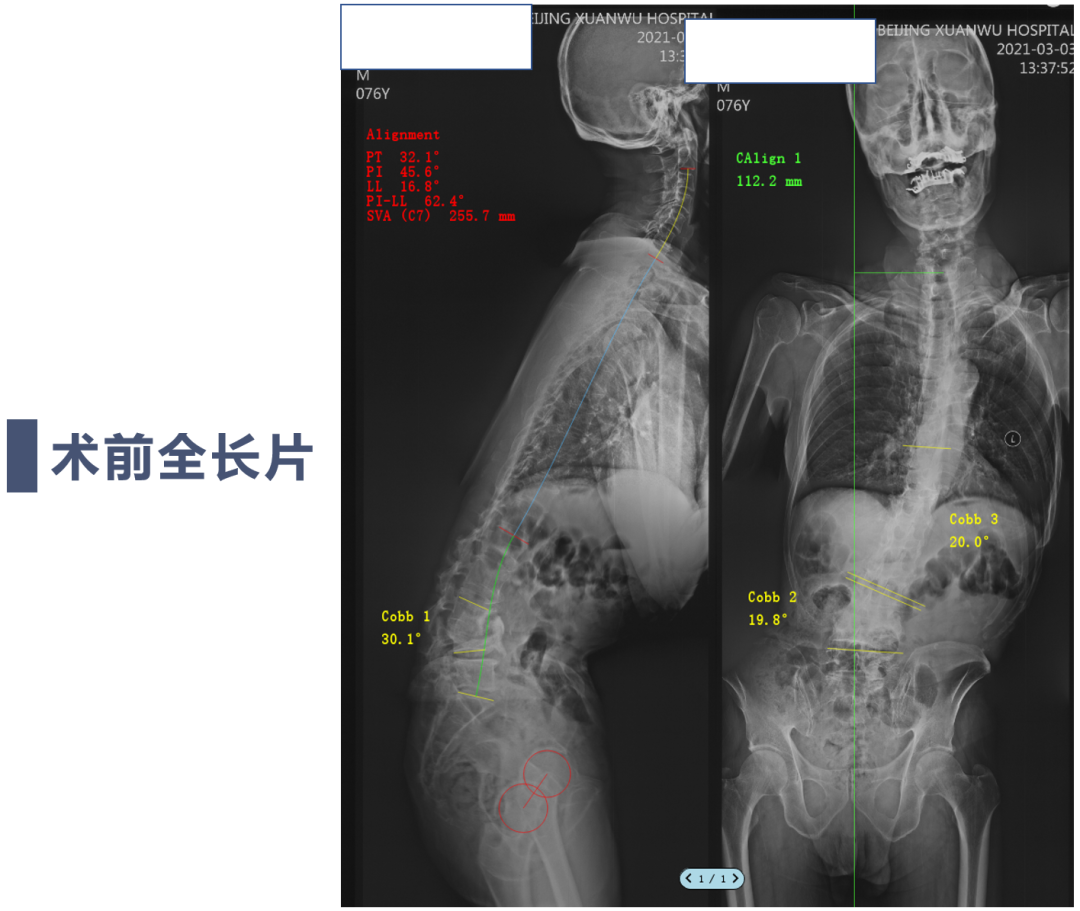

讨论主题:L4压缩骨折伴脊柱侧后凸畸形

影像资料:

腰椎侧后凸畸形

腰椎陈旧性压缩性骨折(L4)